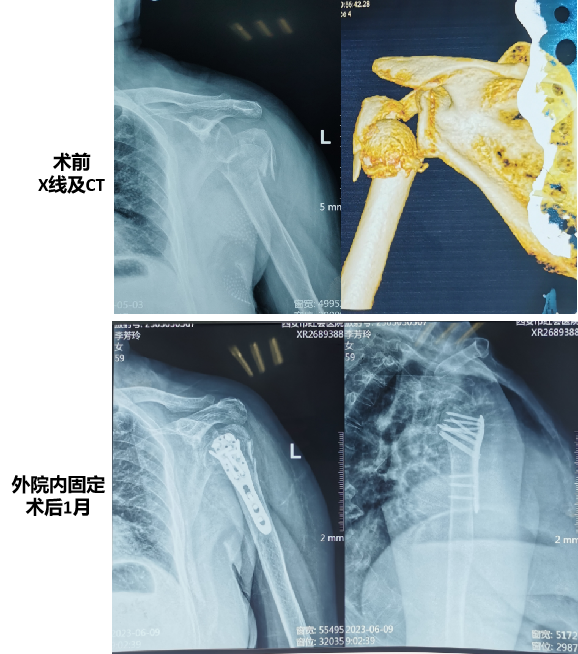

李阿姨在11个月前因受伤导致左肱骨近端粉碎性骨折并伴随左肩关节活动障碍。在外院接受了切开复位内固定手术后,由于同时患有骨质疏松,术后左肱骨近端骨折愈合情况不佳,肱骨头逐渐坏死并被吸收。这一连串的不幸让李阿姨的左肩反复承受剧烈的疼痛,日常活动也受到了极大的限制。疼痛不仅影响了她的睡眠,使她时常在夜间痛醒,更使她的日常生活,如梳头、穿衣、进食等变得异常艰难。李阿姨和家人辗转多家三甲医院寻求治疗,但由于病情复杂,一直未能获得理想的疗效。

就在一周前,经过亲友的推荐,李阿姨来到西安交大二附院运动医学科,找到了时志斌主任。她痛苦地诉说着:“肩部疼痛得让人难以入睡,即使吃了止痛药也无济于事。”面对李阿姨的困境,时志斌主任带领团队进行了详细的检查和评估,最终决定为她实施一种前沿且高效的治疗方式-反肩置换手术,旨在重建和恢复李阿姨的关节功能。在与患者及家属深入沟通后,他们充分理解了手术的必要性和潜在风险,最终决定信任并接受这手术方案。